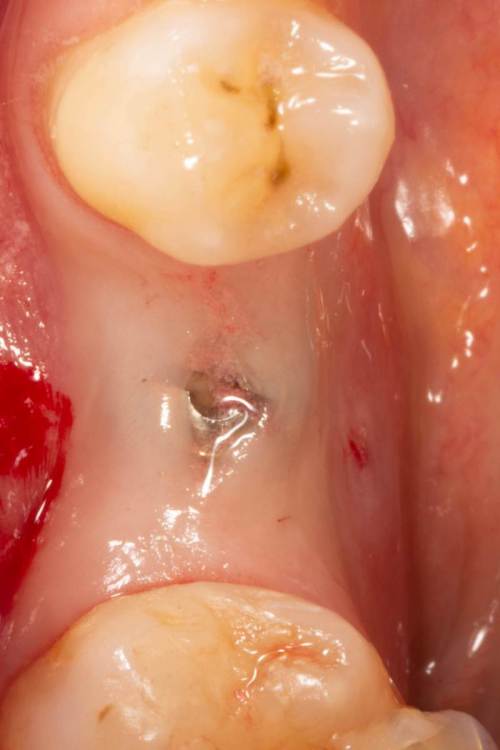

Женька Опубликовано 24 июня, 2023 Поделиться Опубликовано 24 июня, 2023 Собственно похожий случай. Разница лишь в том, что тут заглушка просвечивала. Предоп фоток, к сожалению, нет. 3.6*08мм, тк очень тонко было. Торк при установке потерял. Около 5 примерно был. В данном случае решил сст только вестибулярно положить. p.s. да, налёта много. Пациентка сестра моей одногруппницы, и чистит зубы только у сестры... при встрече я не думал, что чистки давно не было. Косяк, не отрицаю. Фотку со швами забыл сделать. Сделаем на снятии. Ссылка на комментарий

Женька Опубликовано 3 июля, 2023 Автор Поделиться Опубликовано 3 июля, 2023 А здесь вроде результат получше, как считаете? 1 Ссылка на комментарий

TIGER Опубликовано 5 июля, 2023 Поделиться Опубликовано 5 июля, 2023 @Женька что не нравится?не вижу криминала тут Ссылка на комментарий